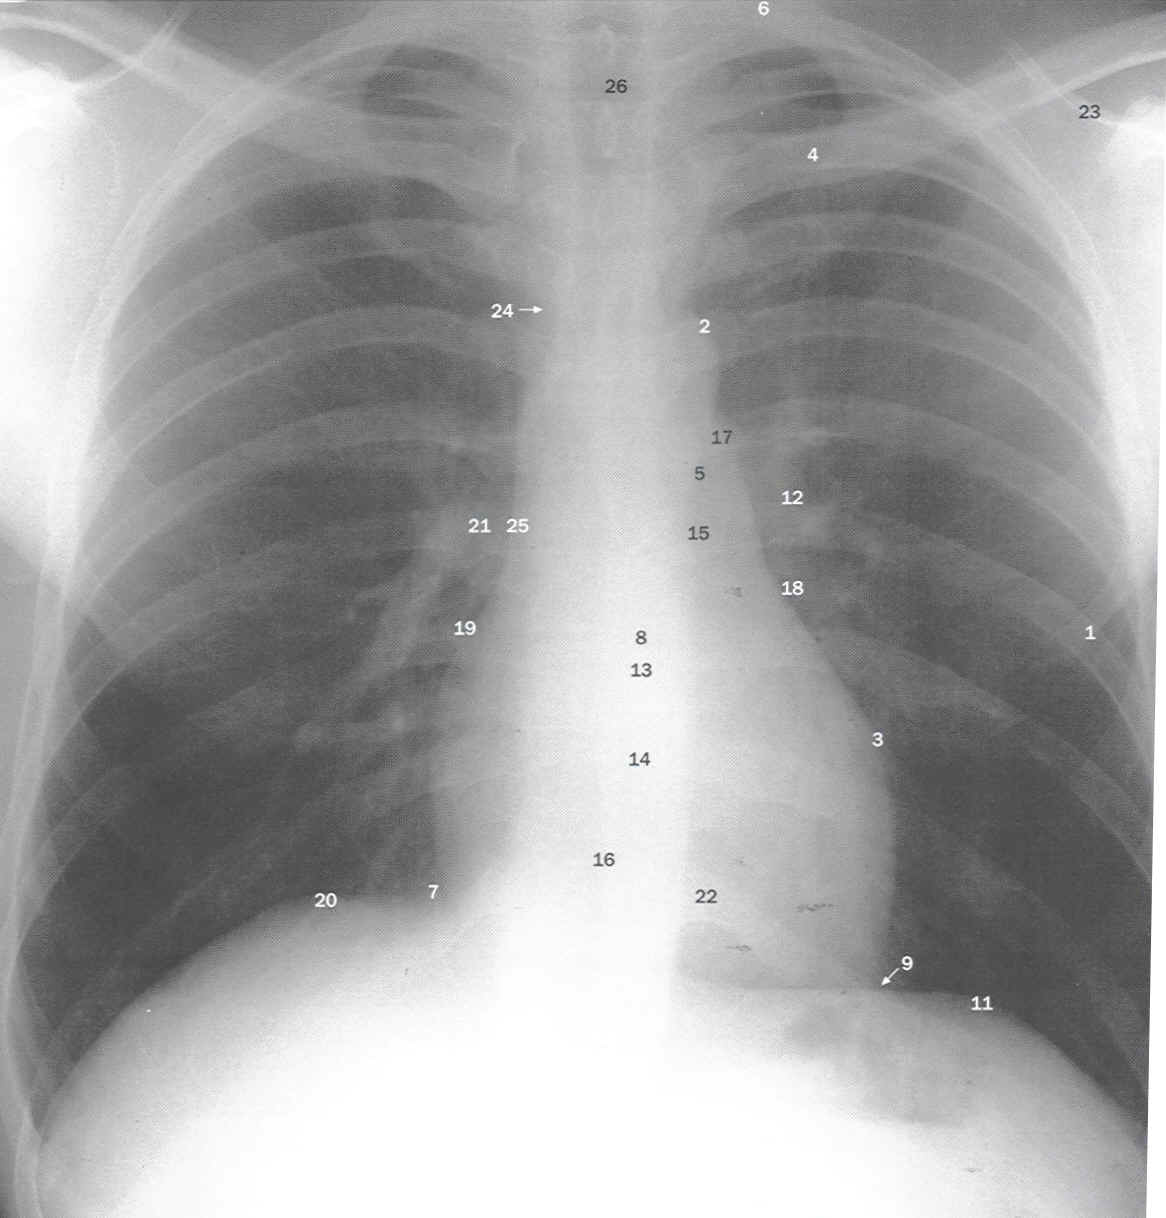

Radiologia Torácica